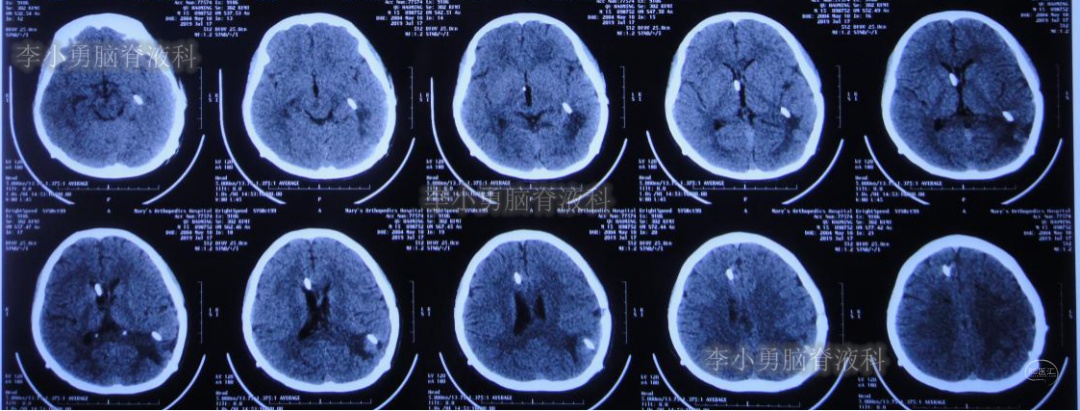

次日2019年4月3日(脑出血后8天),转至河南省郑州市某三甲医院;入院当日头颅CT(图-5)及CTA(图-6)检查结果:出血量较昨日无增加,动脉血管未见明显异常。

图-5:2019年4月3日头颅CT:出血量无增加

图-6:2019年4月3日头颅CTA:未见明显异常

继续给予脑室外引流1周后即2019年4月11日,再次复查头颅CT(图-7):脑室内积血明显减少,脑室不大。

图-7:2019年4月11日头颅CT:脑室内积血明显减少